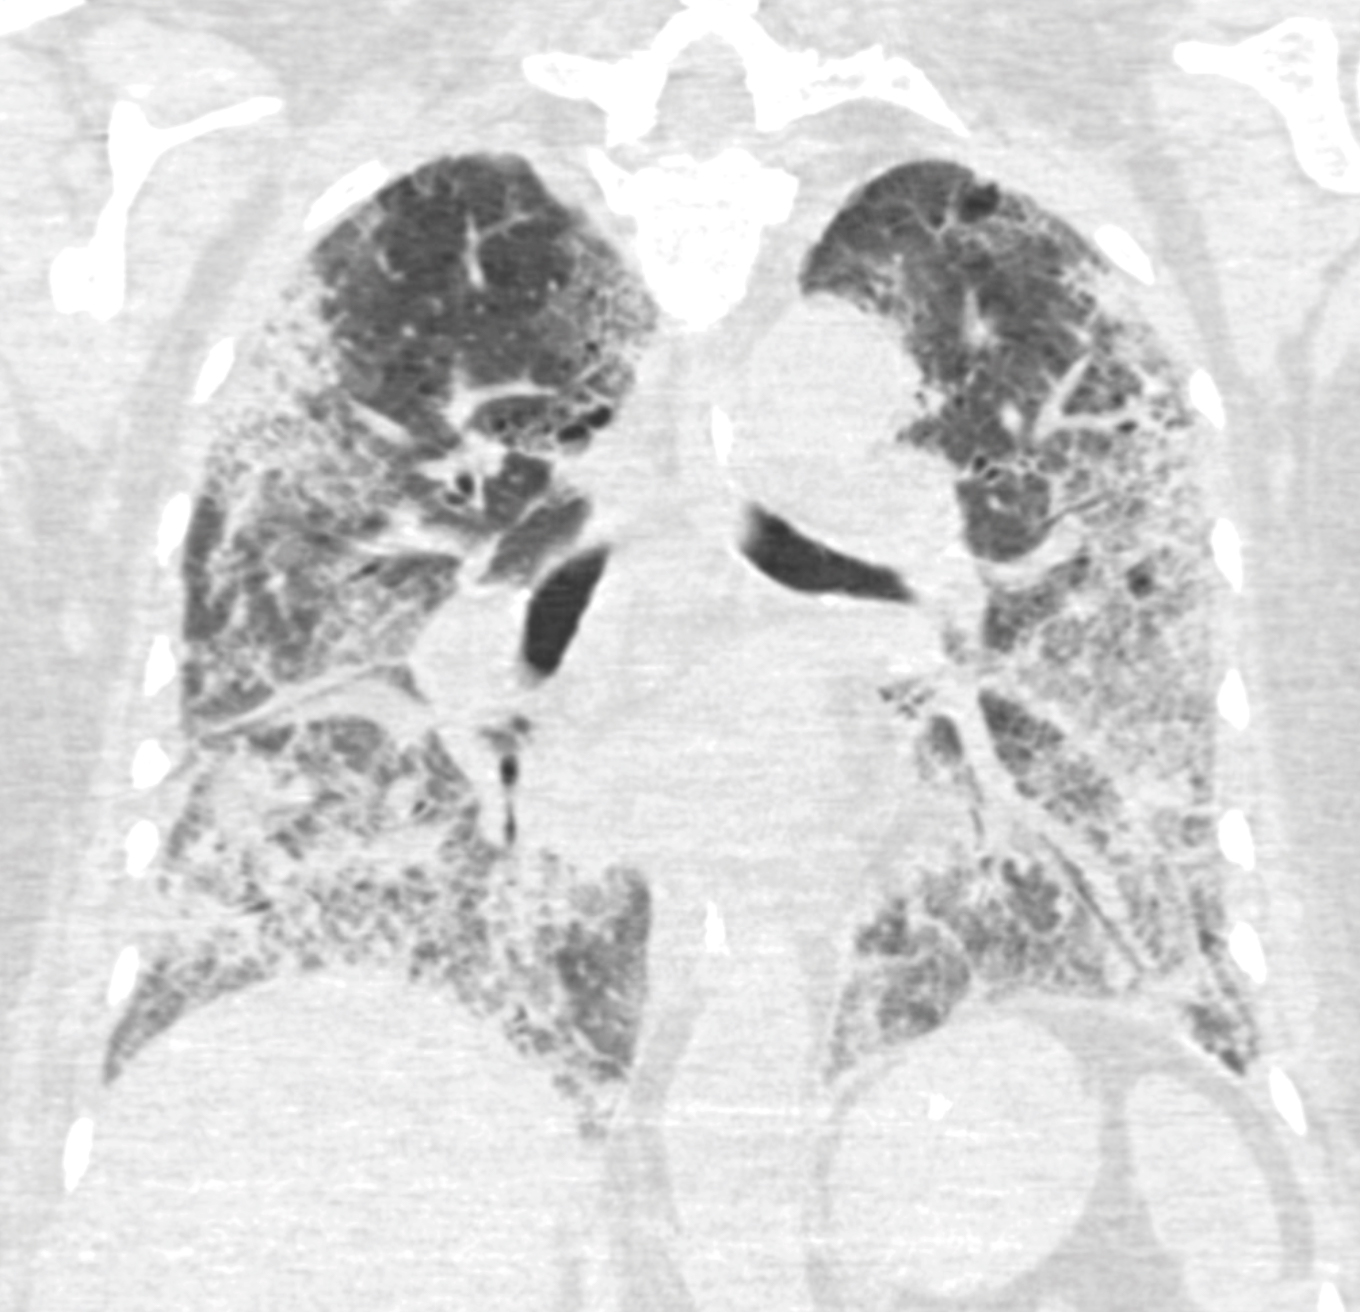

18 dager etter innleggelse viste CT (figur 2) bilaterale lungefortetninger og perifere lungeembolier. Den profylaktiske dosen med blodfortynnende som pasienten hadde fått siden hun ble lagt på respirator (dalteparin 5 000 E × 1 subkutant), ble derfor økt til vektjustert behandlingsdose for lungeemboli (12 500 E × 1 subkutant). CRP-verdien var vedvarende høy til tross for bredspektret antibiotikabehandling, og pasienten ble for tredje gang betydelig O2-krevende, med uendret respiratorinnsats.